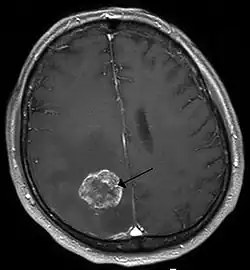

| Brain metastasis in the right cerebral hemisphere from lung cancer, shown on magnetic resonance imaging | |